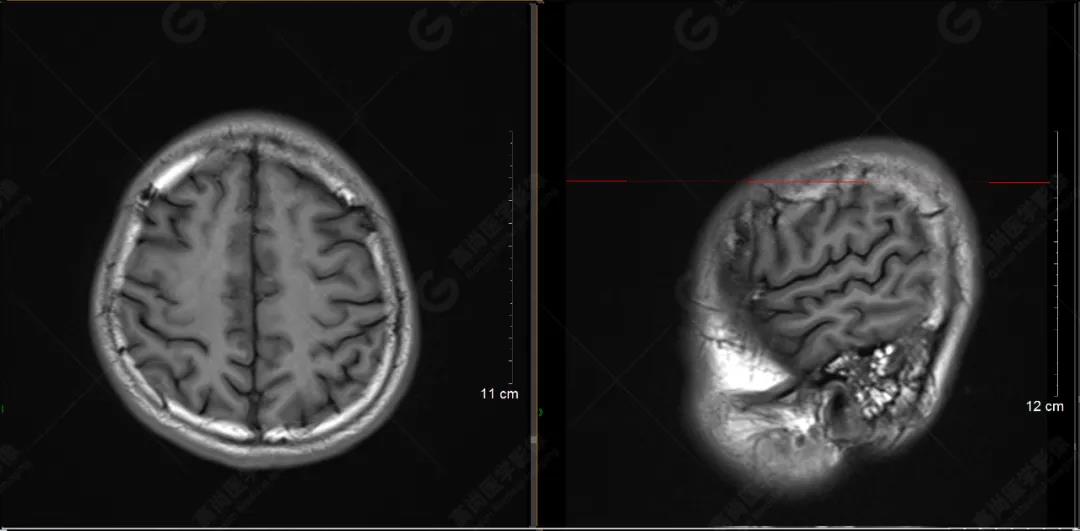

(左側(cè)為薄層原始圖像,右側(cè)為后處理5mm圖像)

SWI序列影像表現(xiàn)及診斷

左側(cè)額底及左側(cè)顳葉內(nèi)見多發(fā)斑點狀極低信號影??紤]額顳葉多發(fā)腦挫傷伴微出血、含鐵血黃素沉著,左側(cè)乳突骨折、乳突內(nèi)積血。討論:1、SWI利用不同組織間磁敏感的差異成像并將其放大,通過檢測病灶中的靜脈分布、出血灶和礦物質(zhì)沉積等,有效改善了相關(guān)疾病的診斷,主要應(yīng)用于中樞神經(jīng)系統(tǒng)。2、根據(jù)磁距圖像和相位圖像表現(xiàn),對于鑒別顱內(nèi)出血及鈣化有一定程度的價值,用于彌補(bǔ)MRI對鈣化顯示的不足。